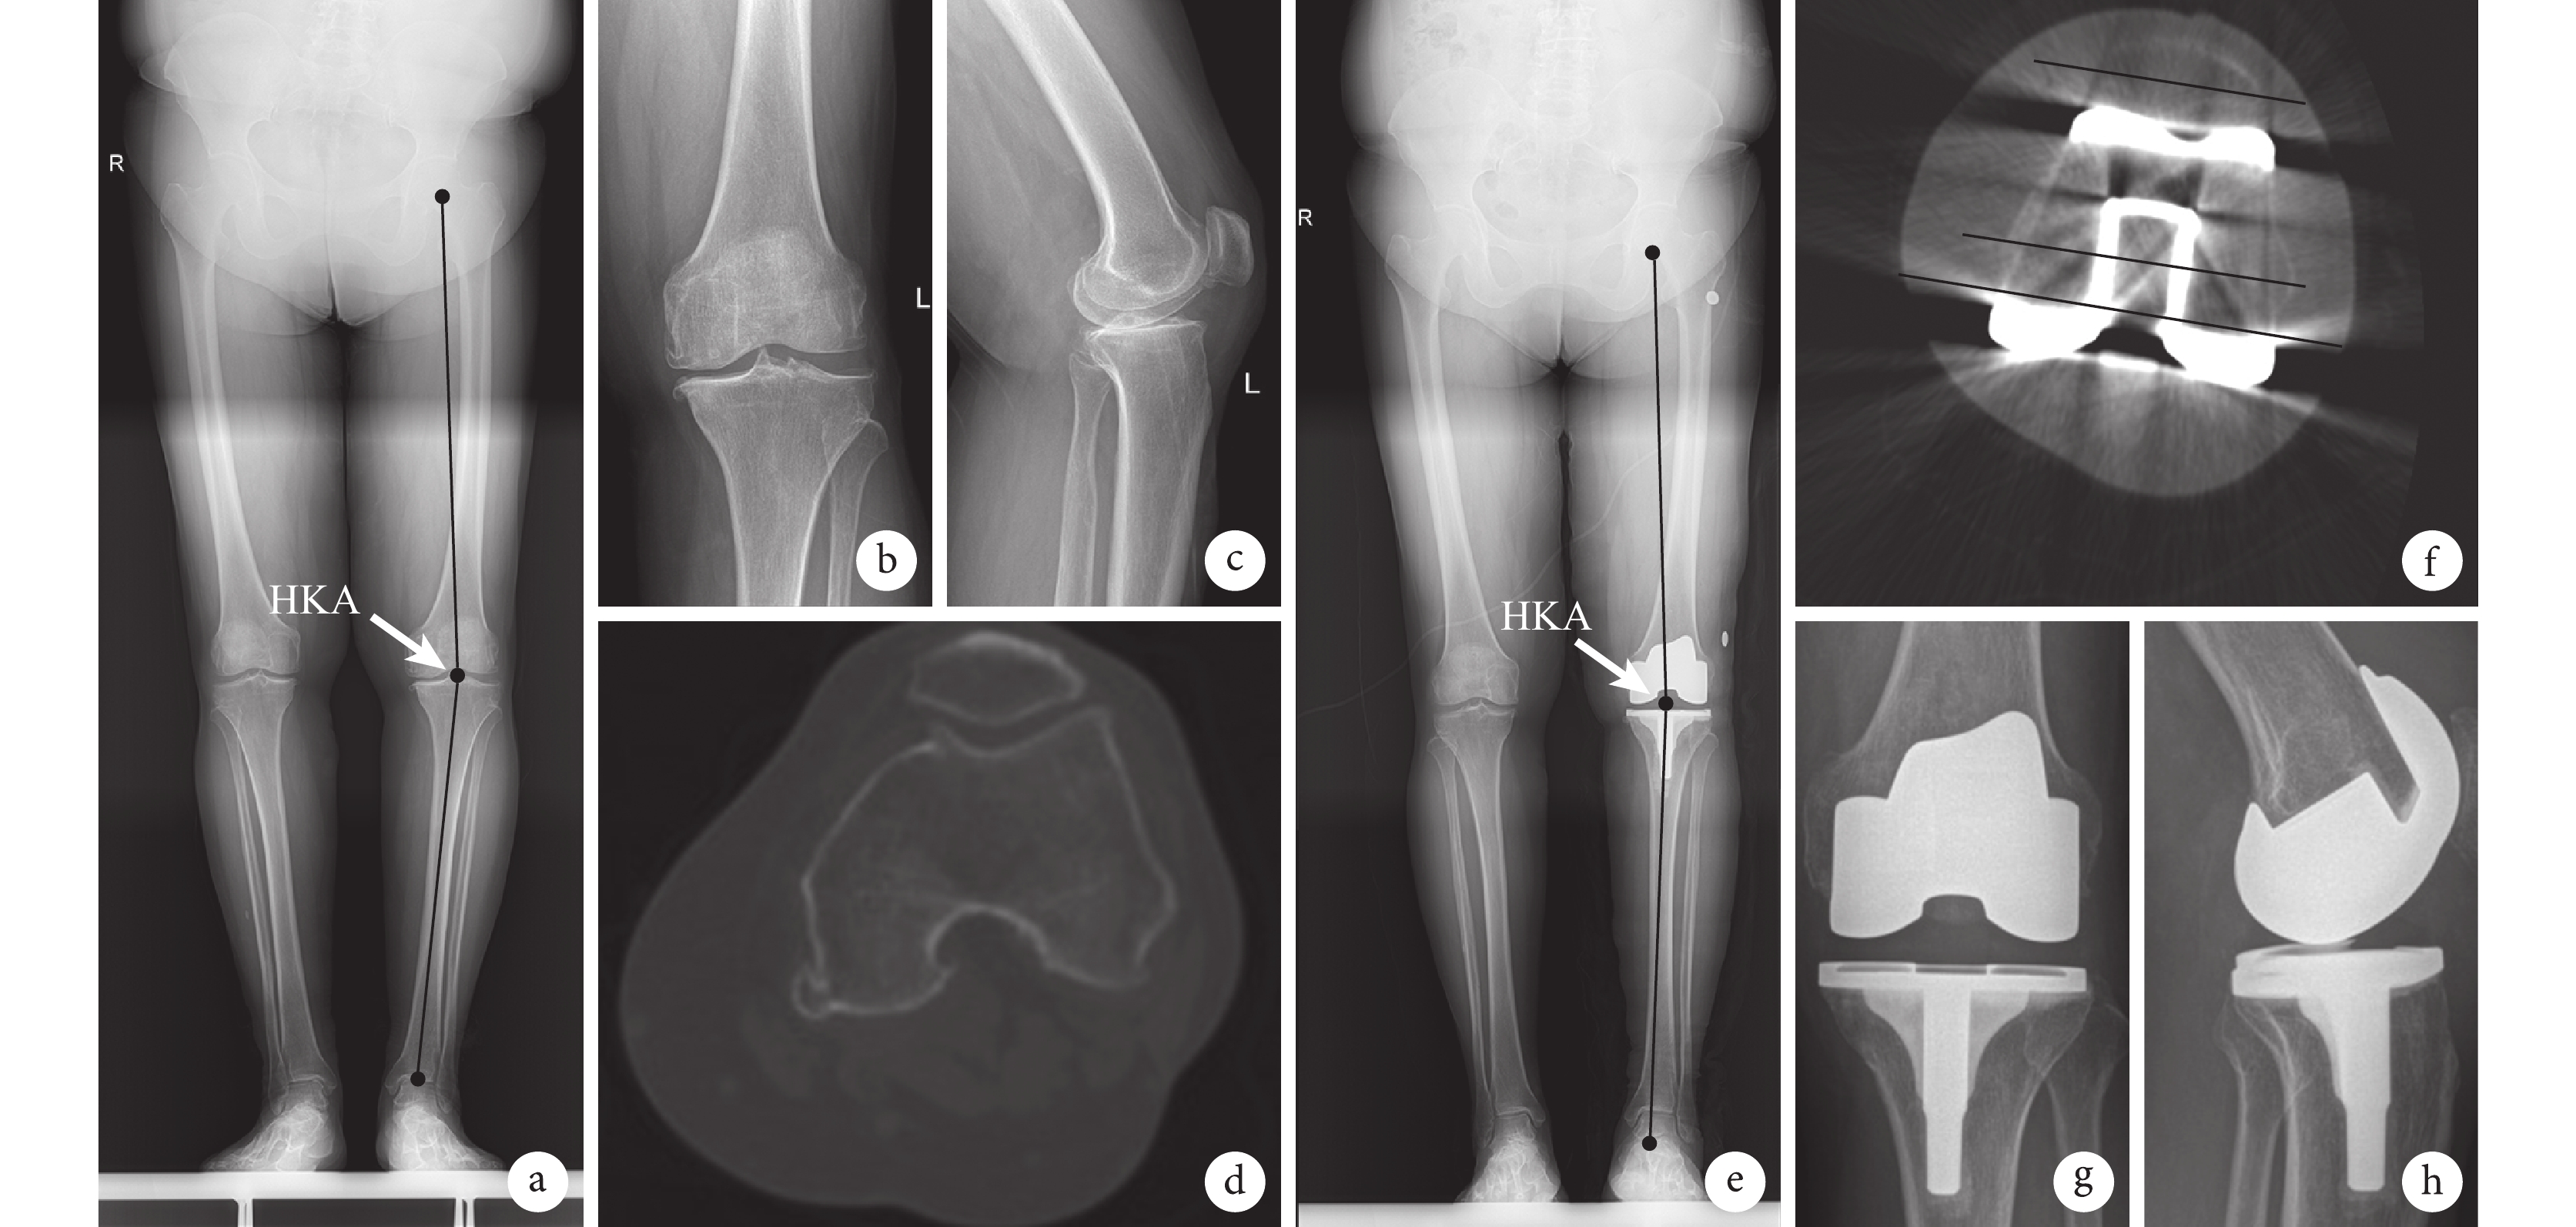

手術組患者術后切口均Ⅰ期愈合,無手術相關并發癥發生。患者均獲隨訪,隨訪時間 7~12 個月,平均 9.0 個月。術后 6 個月 WOMAC 評分及 VAS 評分均優于術前,差異有統計學意義(P<0.05),見表 1。影像學復查示,術后 4 周 HKA 為(178.8±0.8)°,與術前比較,差異有統計學意義(t=39.203,P=0.000);假體位置良好,股骨后髁截骨線、外科通髁線及髕骨橫軸平行,內翻畸形均矯正,下肢力線恢復至中立位。見圖 3。

a. 術前下肢全長 X 線片;b. 術前膝關節正位 X 線片;c. 術前膝關節側位 X 線片;d. 術前膝關節 CT;e. 術后 4 周下肢全長 X 線片;f. 術后 4 周 CT 顯示外科通髁線、后髁截骨線、髕骨橫軸三者平行;g. 術后 6 個月膝關節正位 X 線片;h. 術后 6 個月膝關節側位 X 線片

Figure3. A 60-year-old female patient with osteoarthritis of left knee (Kellgren-Lawrence Ⅳ level)a. Preoperative X-ray film of the full-length lower extremity; b. Preoperative anteroposterior X-ray film of the knee; c. Preoperative lateral X-ray film of the knee; d. Preoperative CT of the knee; e. X-ray film of the full-length lower extremity at 4 weeks after operation; f. CT at 4 weeks after operation showed that the femoral posterior condyle osteotomy line, surgical transepicondylar axis, and patella transverse line were parallel; g. Anteroposterior X-ray film of the knee at 6 months after operation; h. Lateral X-ray film of the knee at 6 months after operation